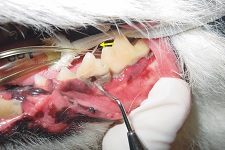

Furcation Defect April 2009-02

A grade 3 furcation defect on this cats mandibular molar (marked with yellow a), compared to the 4th mandibular premolar where there is no radiographic evidence of a furcation defect